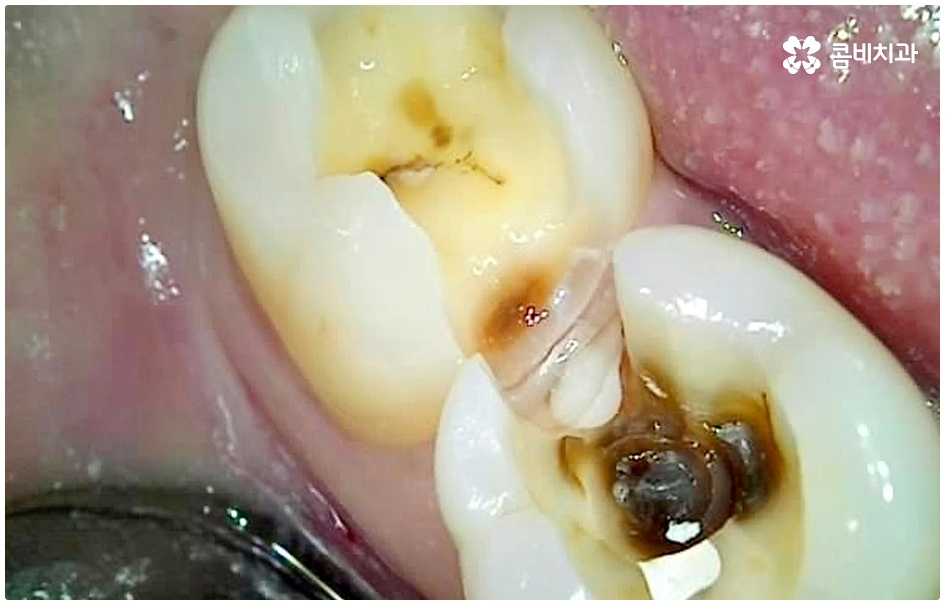

충치가 심해지면 치아가 부서지기도 하고 치수 내부까지 감염되면 극심한 동통을 일으키는 치수염으로 진행되기도 하기 때문에 그 전에 명동치과 치료를 해 주실 필요가 있어요. 충치는 하루 아침에 갑자기 상태가 나빠진다기 보다는 세균이 안쪽으로 침투하면서 손상이 단계적으로 심해지는 구강 질환이기 때문에 쑤시거나 시큰거리는 증상이 느껴지면 초기에 바로 명동치과 로 내원하셔서 검진 및 치료를 받는 것이 중요하다고 할 수 있는데요.

이 때 교합면, 즉 치아의 씹는 면이 아닌 치아 사이 충치가 생겼다면 쉽게 발견하기도 어렵고 치료를 위한 접근 역시 까다롭기 때문에 주의하실 필요가 있습니다. 물론 가장 흔하게 발생하는 것은 넓고 홈이 파여 있으며 직접 음식물을 저작하는 교합면에 생기는 충치일 것이나 음식물 찌꺼기가 끼기 쉽고 세균이 서식하기도 쉬우며 양치질을 하더라도 칫솔모가 잘 닿지 않기 때문에 관리가 어려운 치아 사이 좁은 틈새에도 역시 충치가 잘 생길 수 있는 거예요.

치아 사이 충치는 치아끼리 맞닿아 있는 부분이라 노출이 잘 되지 않기 때문에 육안으로 식별이 어려운 경우가 많은데, 만약 눈으로 확인될 정도라면 질환이 이미 많이 진행한 상태이므로 명동치과 에서 빠른 치료를 받아주실 필요가 있어요.

치아의 구조를 살펴보면 겉표면인 단단한 법랑질은 교합면에서 가장 두껍고 잇몸쪽으로 갈수록 얇아지기 때문에 치아 사이의 인접면은 치아의 신경과 한층 가까워서 충치가 조금만 진행되어도 신경치료를 받아야 할 수 있으며 인접면 충치가 심하여 레진이나 인레이 수복으로 치아의 외형을 재현하기 어려운 경우에는 치아 전체를 다듬어 씌우는 명동치과 크라운 치료를 해줘야 하니 부담이 커지기 전에 치료 시기를 놓치지 않도록 주의하시는 게 좋을 거예요.